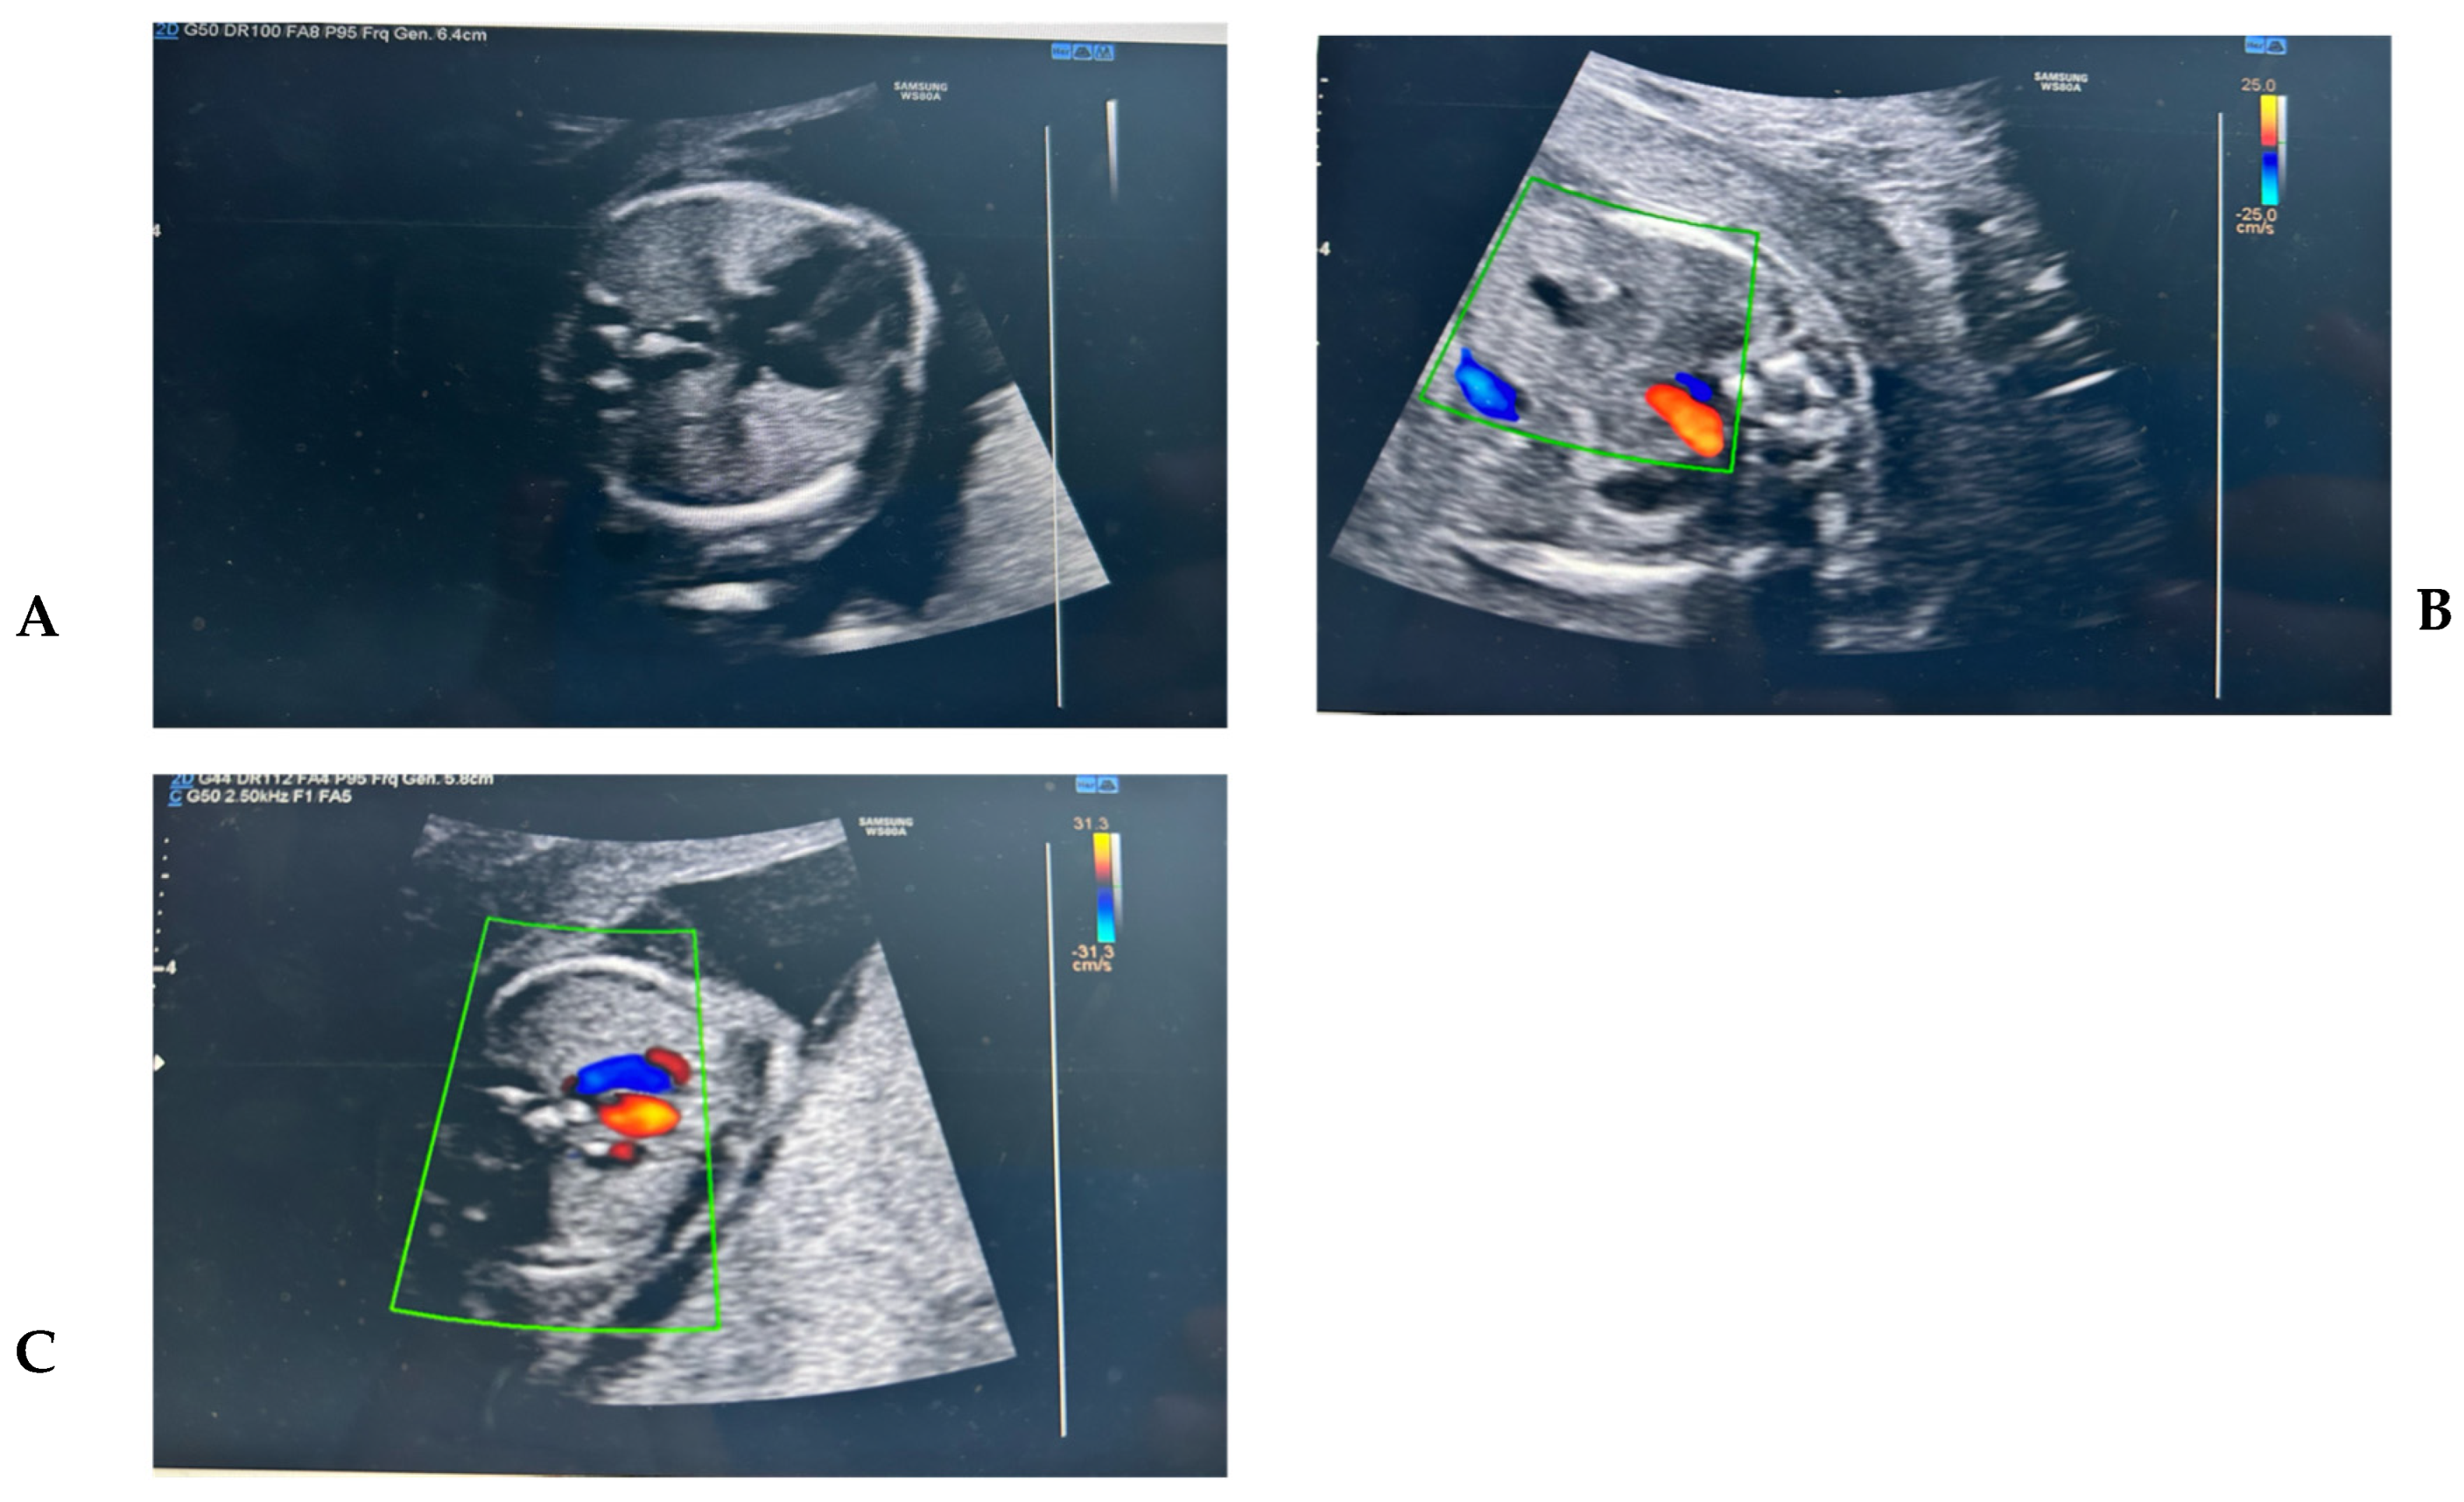

Figure 1. (A) The four-chamber view shows a dilated azygos vein (Az) located posterior to the descending aorta (Ao), a finding known as the “double vessel sign.” (B) The normal vascular conformation at this level typically includes the aorta (Ao) located near the spine on the left, a small and usually non-visualized azygos vein, and the inferior vena cava (IVC) positioned anterior and to the right of the aorta. (C) The three-vessel and trachea (3VT) view shows a dilated azygos vein (Az) draining into the superior vena cava (SVC). This finding reflects a compensatory mechanism in cases of interrupted inferior vena cava (IVC) with azygos continuation.

A 35-year-old woman, gravida 2 para 1, presented for a second-trimester morphological ultrasound at 20 weeks of gestation. She had previously delivered vaginally after a pregnancy with a normal karyotype confirmed by chorionic villus sampling. During that first pregnancy, she had undergone an invasive procedure due to an increased nuchal translucency detected at the first-trimester scan. The current pregnancy had been uneventful, with normal non-invasive prenatal testing and a reassuring first-trimester ultrasound. During the anomaly scan, an abnormal venous return was identified. A vessel was noted posterior to the descending aorta in the four-chamber view, consistent with the “double vessel sign.” Further examination in the bicaval view revealed absence of the intrahepatic segment of the IVC, and a dilated superior vena cava (SVC) was evident in the three-vessel view. A thinner vessel was traced from the infrahepatic IVC to the SVC, indicating azygos continuation. The patient was referred to a tertiary center for fetal echocardiography, which confirmed the diagnosis. Genetic counseling was offered, but the patient declined invasive testing and opted to continue the pregnancy. A male infant weighing 2.8 kg was delivered vaginally at 38 weeks of gestation. The neonatal course was uneventful. Postnatal echocardiography performed at 6 weeks confirmed the prenatal diagnosis of isolated IVC interruption with azygos continuation. No cardiac or extracardiac abnormalities were found. The infant was scheduled for routine follow-up due to the theoretical risk of arrhythmias or venous insufficiency in later life. (Figure 1A) The four-chamber view shows a dilated azygos vein (Az) located posterior to the descending aorta (Ao), a finding known as the “double vessel sign”. (Figure 1B)The normal vascular conformation at this level typically includes the aorta (Ao) located near the spine on the left, a small and usually non-visualized azygos vein, and the inferior vena cava (IVC) positioned anterior and to the right of the aorta. (Figure 1C) The three-vessel and trachea (3VT) view shows a dilated azygos vein (Az) draining into the superior vena cava (SVC). This finding reflects a compensatory mechanism in cases of interrupted inferior vena cava (IVC) with azygos continuation.